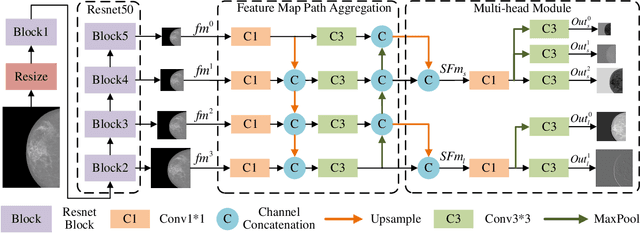

Multi-Head Feature Pyramid Networks for Breast Mass Detection

Feb 22, 2023

Analysis of X-ray images is one of the main tools to diagnose breast cancer. The ability to quickly and accurately detect the location of masses from the huge amount of image data is the key to reducing the morbidity and mortality of breast cancer. Currently, the main factor limiting the accuracy of breast mass detection is the unequal focus on the mass boxes, leading the network to focus too much on larger masses at the expense of smaller ones. In the paper, we propose the multi-head feature pyramid module (MHFPN) to solve the problem of unbalanced focus of target boxes during feature map fusion and design a multi-head breast mass detection network (MBMDnet). Experimental studies show that, comparing to the SOTA detection baselines, our method improves by 6.58% (in AP@50) and 5.4% (in TPR@50) on the commonly used INbreast dataset, while about 6-8% improvements (in AP@20) are also observed on the public MIAS and BCS-DBT datasets.